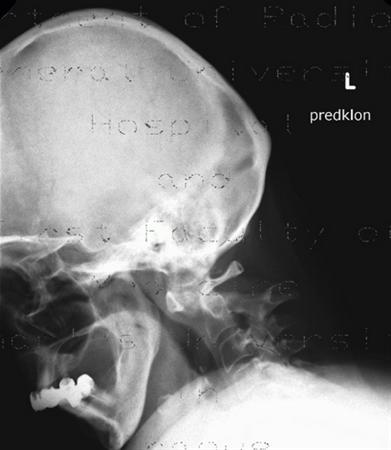

1. A 79-year old man falls sustaining a hyperextension injury to his neck. A lateral radiograph, CT scan and MRI are seen in Figures A through C. On motor examination, he has 3/5 strength in his deltoids, elbow and wrist flexors and extensors. He has 4/5 strength in his hip flexors, knee flexors, extensors, ankle dorsiflexors and plantarflexors. Sensation is preserved in both his upper and lower extremities as well as his sacral segments. Injury to which of the following tracts contributes greatest to his motor function deficits?

FIGURES: A

B

C

DISCUSSION: The clinical scenario describes a patient with central cord syndrome, resulting in an injury to his lateral corticospinal tract. Figures A through C show a spondylytic spine with central narrowing and CSF effacement that is worse at the C4-5 level. The lateral corticospinal tract is the main descending motor tract (Illustration A). Its anatomic position places the upper extermity motor tracts at greater risk than the lower extremity tracts. As such, injury to the lateral corticospinal tract is characterized by upper greater than lower extremity involvement and motor deficits being more pronounced than sensory deficits.